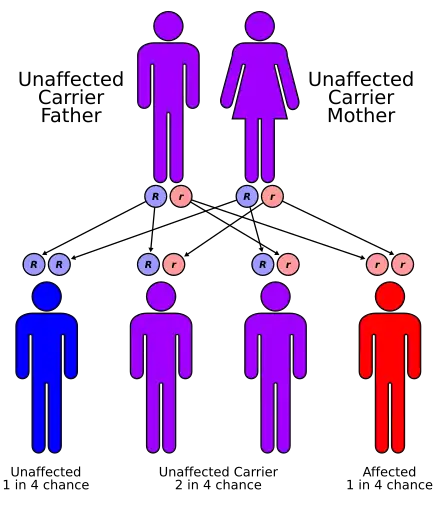

| Craniodiaphyseal dysplasia has an autosomal recessive pattern of inheritance[1] | |

Craniodiaphyseal dysplasia (CDD), also known as lionitis, is an extremely rare autosomal recessive bone disorder that causes calcium to build up in the skull, disfiguring the facial features and reducing life expectancy.